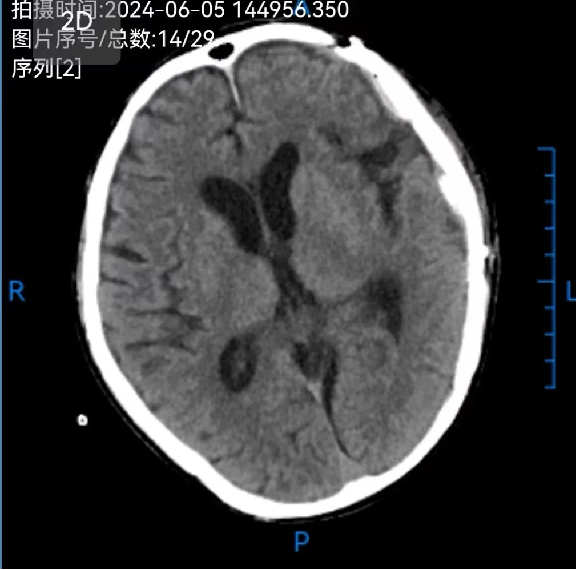

患者汪某,男性,66歲,因重症顱腦(nǎo)損傷,多發肋骨(gǔ)骨折,血氣胸,鎖骨骨折辦理入院緊急手術,醫院神經外科專家團隊為患者行開顱血腫清除+大骨瓣減壓術。手術順利,術後(hòu)恢複滿意。專家團隊將患者手術去除的顱骨骨瓣進行了清洗、滅菌後低(dī)溫冰凍儲存。

患者術後滿三個月(yuè)再次返院進(jìn)行顱骨缺損(sǔn)修補術,經過完善術前檢查、全(quán)科討論、做好充分手術(shù)準備後,武(wǔ)寧縣總醫院人民醫院院區神(shén)經外科團隊成功為患者完成(chéng)自體顱骨修補術(shù)。

術前: